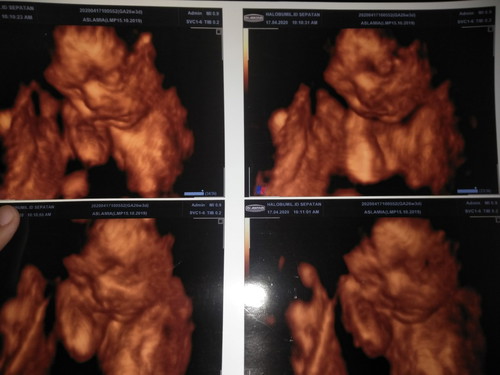

usg

Alhamdulillah sehat 26 minggu